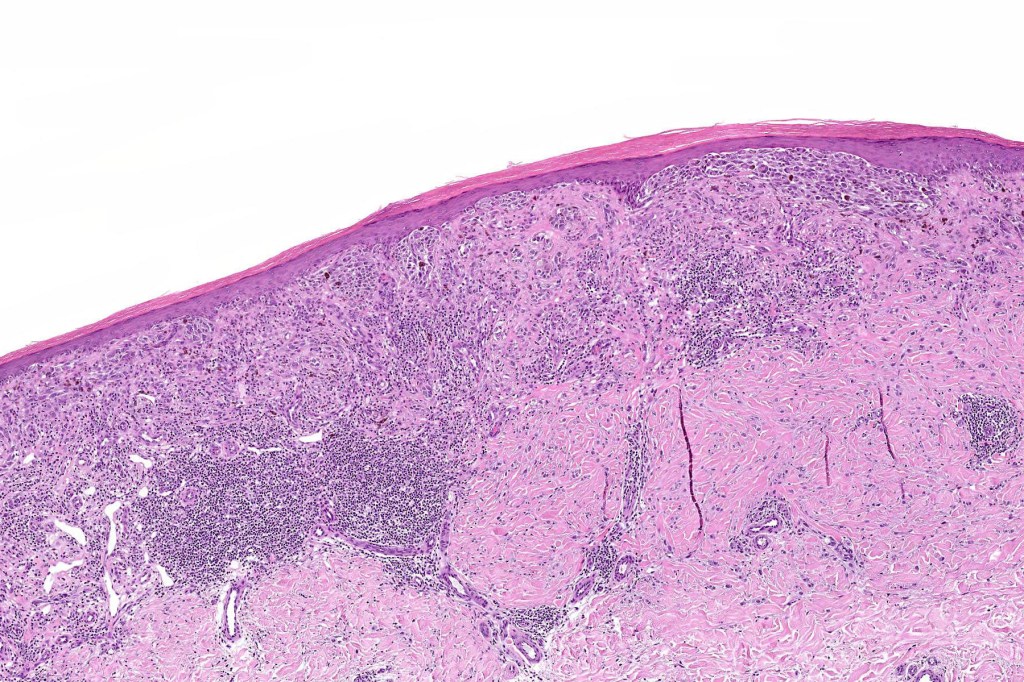

Histological features

•Asymmetrical, poorly circumscribed

•May show effacement/consumption of epidermis or ulceration

•Large nodules which often show impaired maturation

•Loss of gradient with HMB45 and Ki67